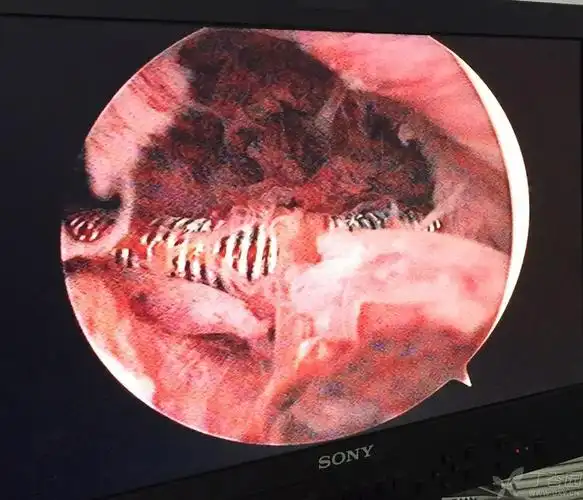

节育环"长进肉里了",垫江县人民医院妇科有办法

环嵌顿宫腔镜下取环

节育环在宫腔形态